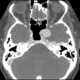

Carotid siphon aneurysm